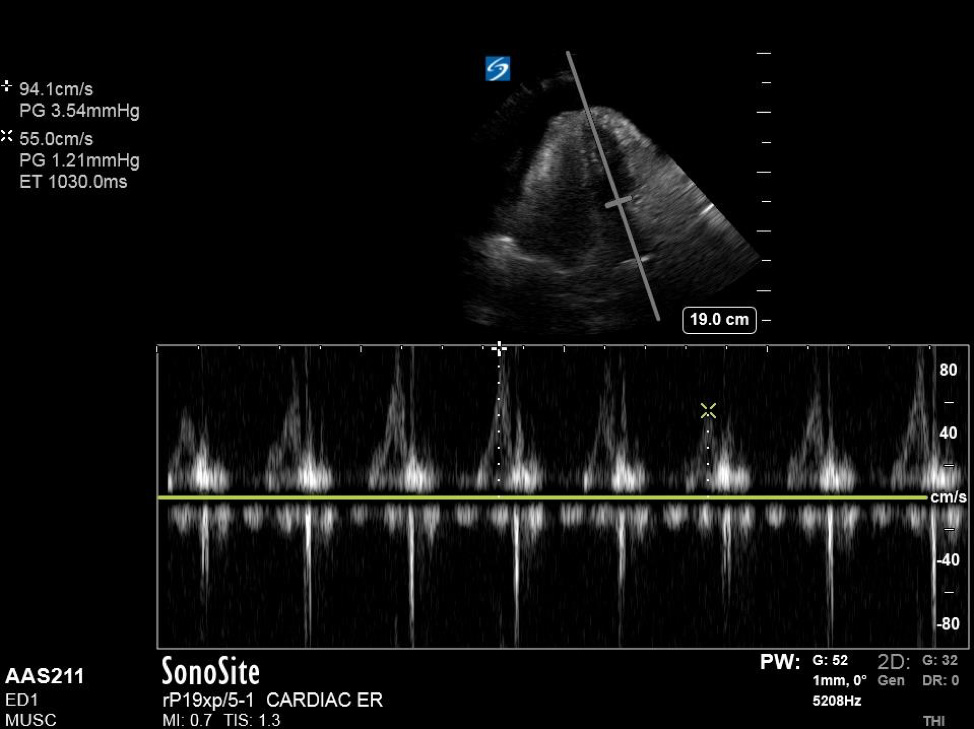

Additionally, when assessing for tamponade, it can be helpful to assess the mitral and tricuspid inflow variation. In pericardial tamponade, there is increased interventricular interdependence during filling exaggerating the respiratory variation flow through the atrioventricular valves. This can be performed in the apical four chamber view, by placing pulse wave doppler (PWD) over the area of either the mitral valve or tricuspid valve. (Figure 4) The velocities are then measured during expiration and inspiration. A mitral valve inflow variation of over 25% or tricuspid valve inflow variation over 40% is indicative of pulsus paradoxus and tamponade physiology. Additional findings in tamponade include a wide, plethoric IVC with minimal variation, as well as collapse of the right atrium during ventricular systole.

Figure 4. Apical 4 chamber view with excessive variation in mitral inflow velocities.